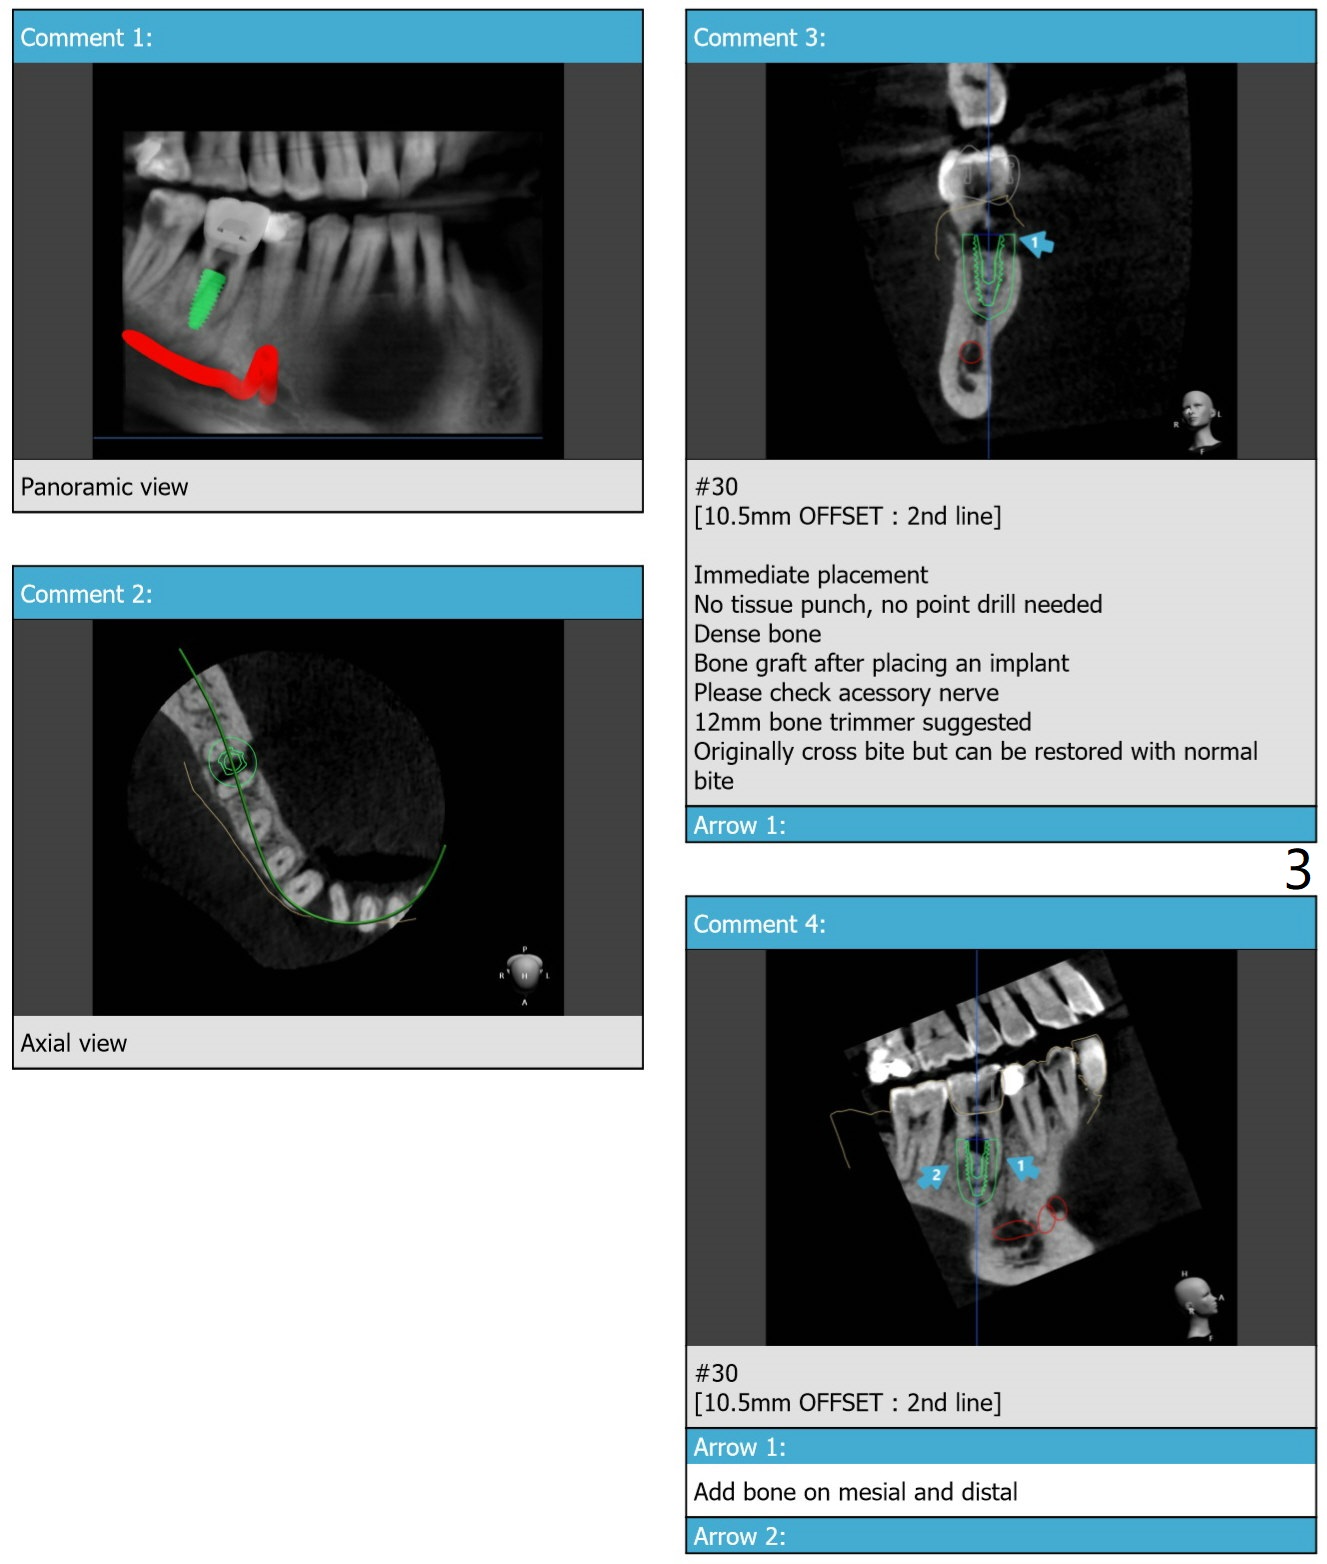

Branch of Inferior Alveolar Nerve